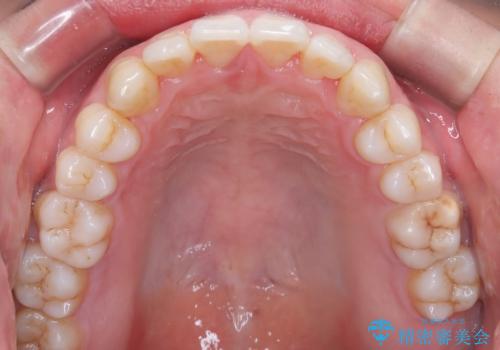

- 前歯のすきっ歯が気になると来院された患者様です。

前歯の隙間をマウスピース矯正(インビザライン)を使用して、閉じていきました。